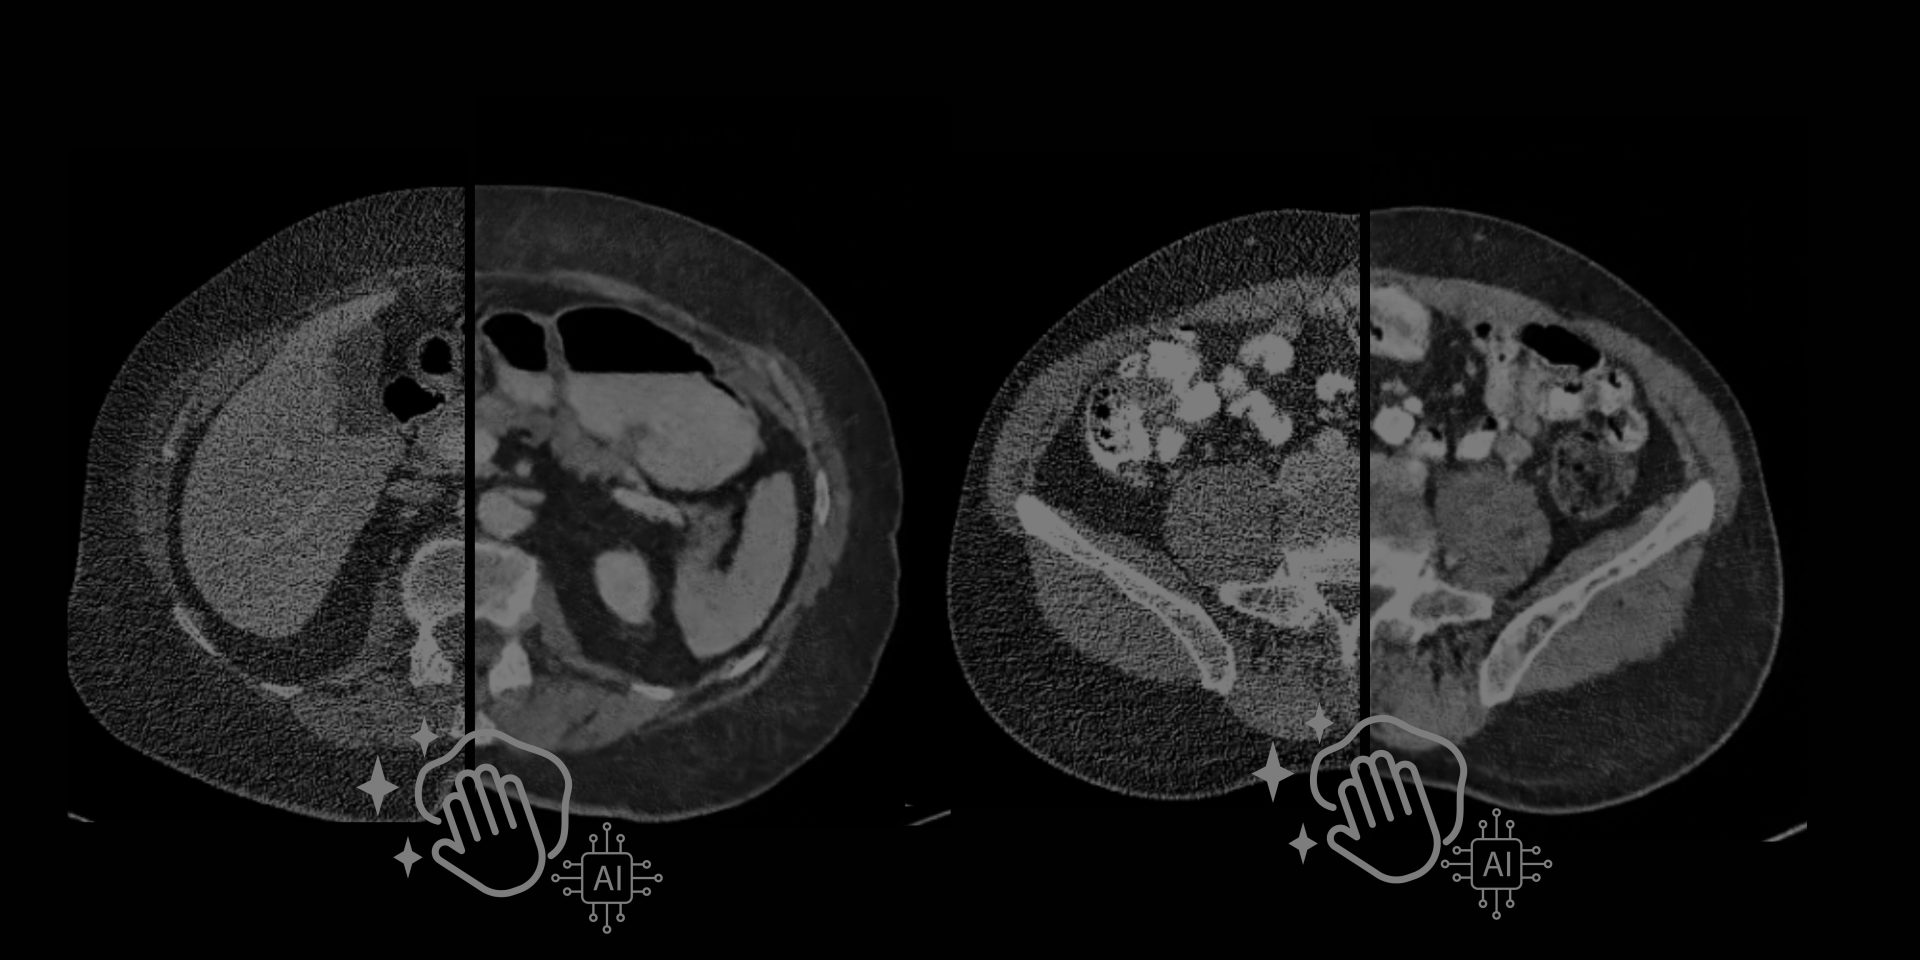

VisionCT2T-En: Deep-learning home-made

Un viaggio nell'applicazione e nello sviluppo di un modello di deep-learning orientato al denoising di immagini TC. Vi racconto com'è andata!